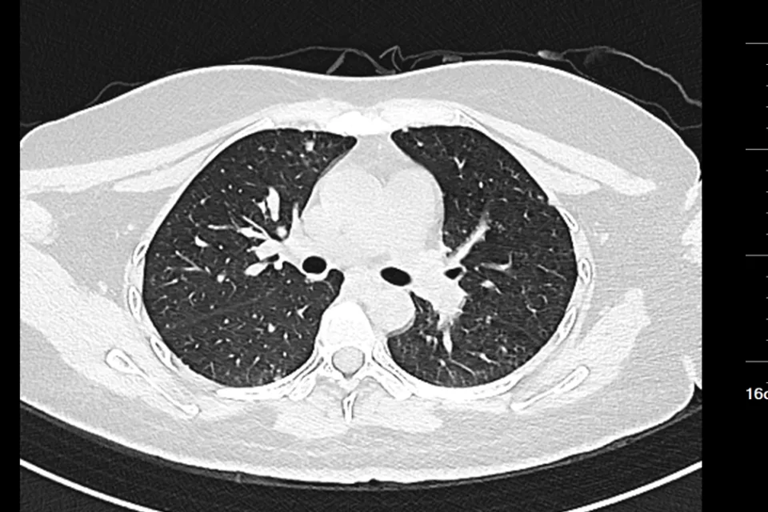

Hình ảnh chụp CT của nữ sinh 20 tuổi

Gần đây, một phụ nữ ngoài 20 tuổi đến khám tại Bệnh viện Nhân dân Đông Hoản (Quảng Đông, Trung Quốc) vì phát hiện khối u ở cổ trái trong khoảng một tuần.

Trước đó, cô cảm thấy vùng cổ đau nhẹ và sờ thấy một khối cứng kích thước gần bằng quả trứng gà. Khối u ấn vào có cảm giác đau nhưng không đỏ, không sưng. Điều đáng nói là cô không hề có triệu chứng tiêu hóa rõ ràng như đau bụng, đầy hơi hay sốt, ăn uống và đại tiện vẫn bình thường.

Sau khi nhập viện để kiểm tra toàn diện, bác sĩ tiến hành nội soi dạ dày và sinh thiết hạch cổ . Kết quả giải phẫu bệnh cho thấy bệnh nhân mắc ung thư biểu mô tuyến kém biệt hóa , trong đó có thành phần ung thư tế bào nhẫn - một dạng ung thư dạ dày ác tính cao.

Chụp CT cho thấy khối u đã di căn toàn thân , không còn chỉ định phẫu thuật. Các bác sĩ chỉ có thể đề nghị điều trị bằng hóa trị, xạ trị hoặc liệu pháp miễn dịch nhằm kiểm soát bệnh.